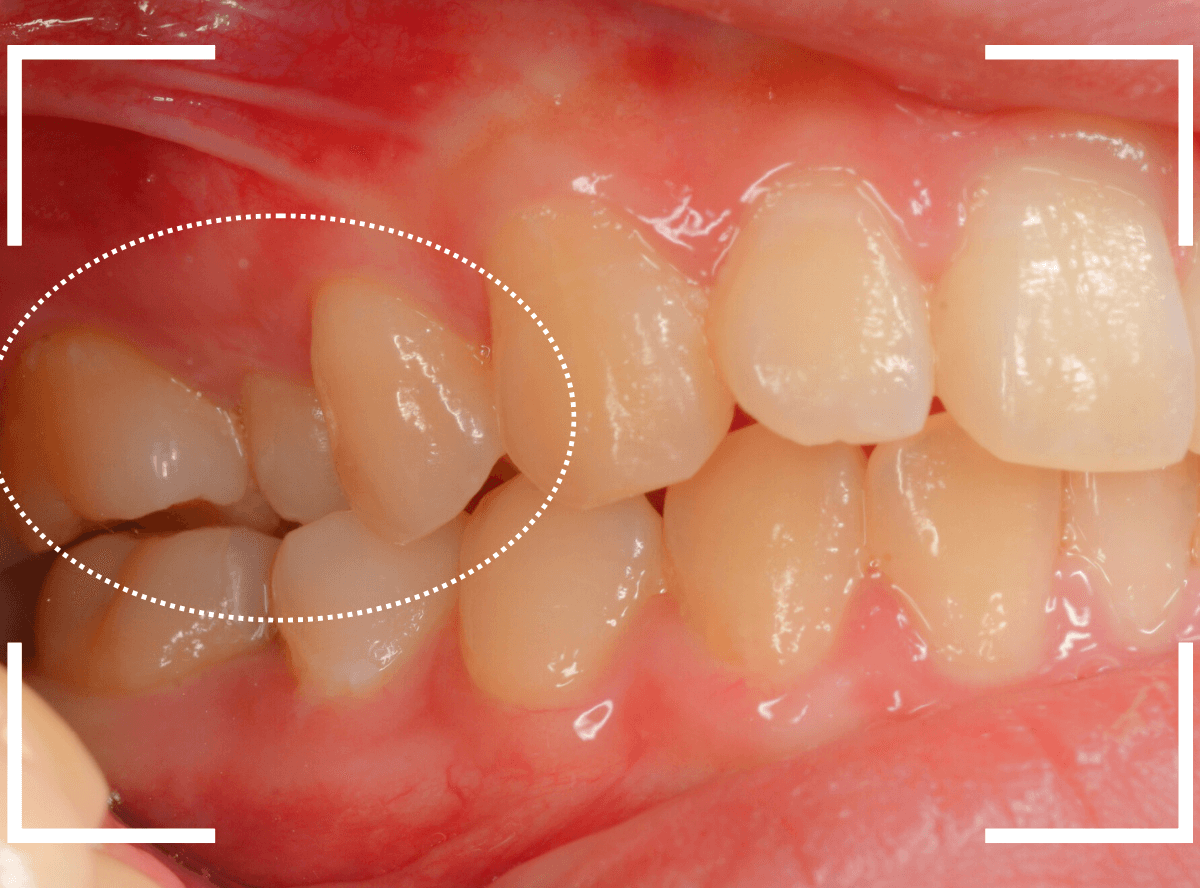

舌のそばの虫歯とセラミック治療

下の奥歯が虫歯になった患者さんのケースです。

〇部が虫歯の部分です。

写真で見てわかるように、常に舌が歯に触っているような状況です。

このような場合、虫歯を見つけづらいですし、治療の難易度もあがります。